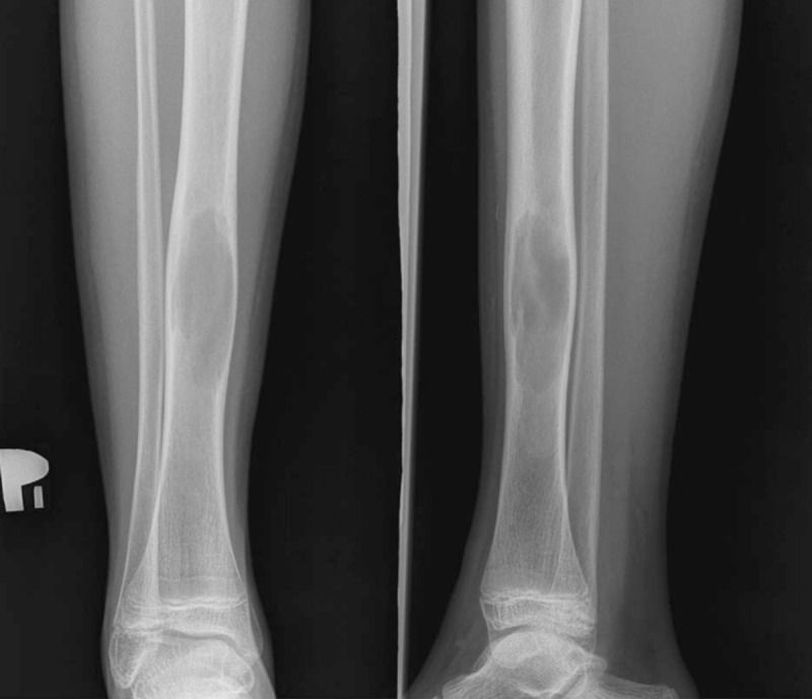

Platelet Rich Plasma (PRP) has become a very popular procedure for cosmetics as well as medical purposes. In past few years, it has been widely used in the healing of wounds, ulcerations and skin injuries. Although it has innumerable benefits, the safety of PRP use is not certain. Here is a case summary of an allergic reaction to PRP treatment. A 14-year-old boy, presented in the hospital with a simple bone cyst of Distal Tibia. After routine labs the patient was qualified for injection of PRP into the site of the bone cyst. An IV anesthesia (propofol ) was administered and a 3 ml of PRP was injected into the cyst. There were no complications during the procedure. However, within the next 24 hours the patient presented with widespread skin rash accompanied by pharyngitis and tonsillar enlargement. A series of prick testing and intradermal testing for serum IgE levels specific for different allergens were conducted, which turned out to be negative. The patient was given Claritine and Clemastin (antihistamines) for the treatment. Within 4 days the symptoms subsided, and the patient was discharged. Reference: Latalski, Michal MD, PhDa,*; Walczyk, Alicja MDb; Fatyga, Marek MD, PhDa; Rutz, Erich MD, PhDc; Szponder, Tomasz MD, PhDd; Bielecki, Tomasz MD, PhDe; Danielewicz, Anna MDa Allergic reaction to platelet-rich plasma (PRP), Medicine: March 2019 - Volume 98 - Issue 10 - p e14702 doi: 10.1097/MD.0000000000014702